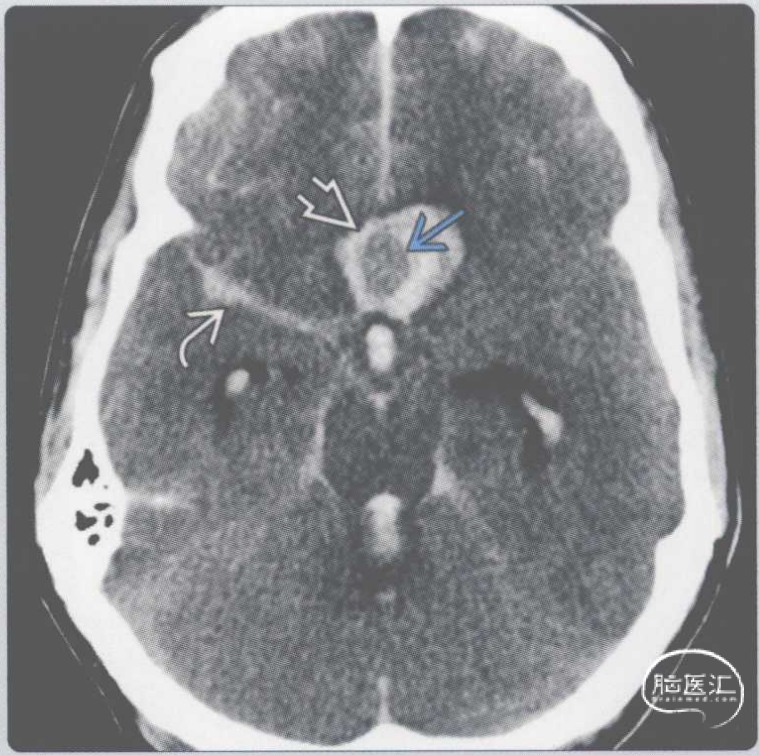

【影像时间·235】一例去氧麻黄碱滥用的32岁女性患者